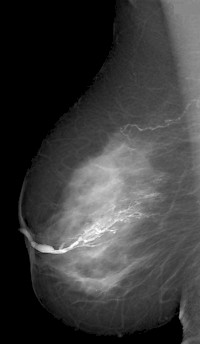

Abb. 1 Unauffällige Galaktographie eines Milchgangs - Foto:Wikipedia

Die Galaktographie ist ein mammografisches Zusatzverfahren zur Darstellung der Milchgänge. Zu diesem Zweck wird ein Kontrastmittel mit Hilfe eines dünnen Plastikschlauches in den sekretierenden Milchgang gespritzt und anschließend eine Röntgenaufnahme angefertigt.

Das Untersuchungsergebnis wird als Galaktogramm bezeichnet und stellt intraduktale Veränderungen dar.

Die Galaktografie dient dazu, einen Tumor oder ein Papillom im Milchgang zu entdecken und zu lokalisieren, damit die Veränderung in einer anschließenden Operation entfernt werden kann.